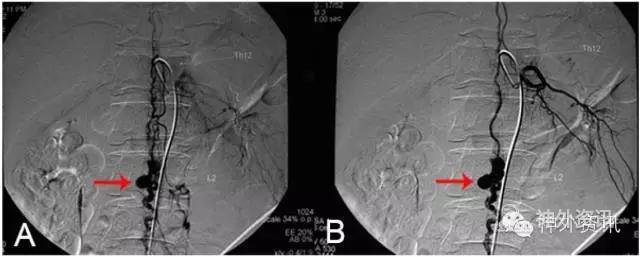

图13: 左肾静脉狭窄致脊髓静脉高压综合征,红色↑示肾静脉狭窄,绿色↑示向肾椎静脉回流。